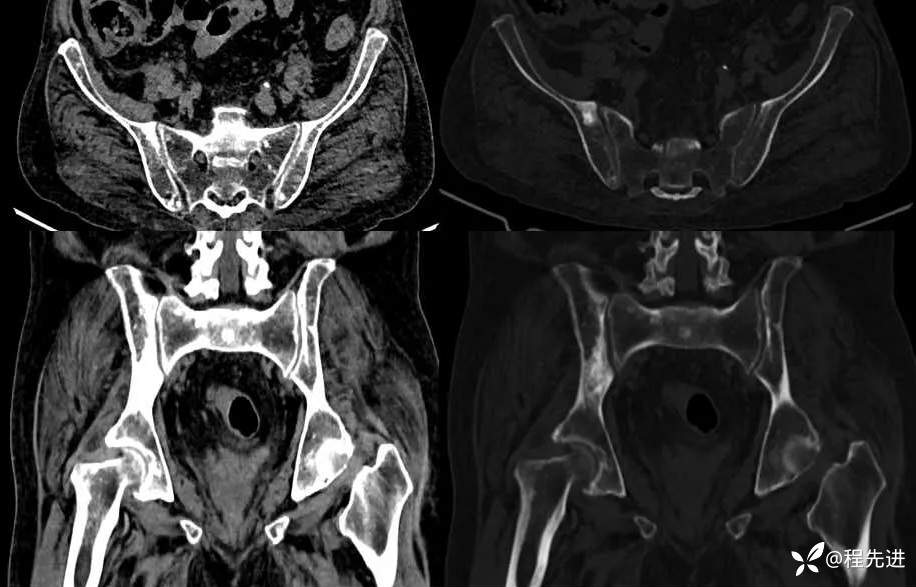

骨盆: